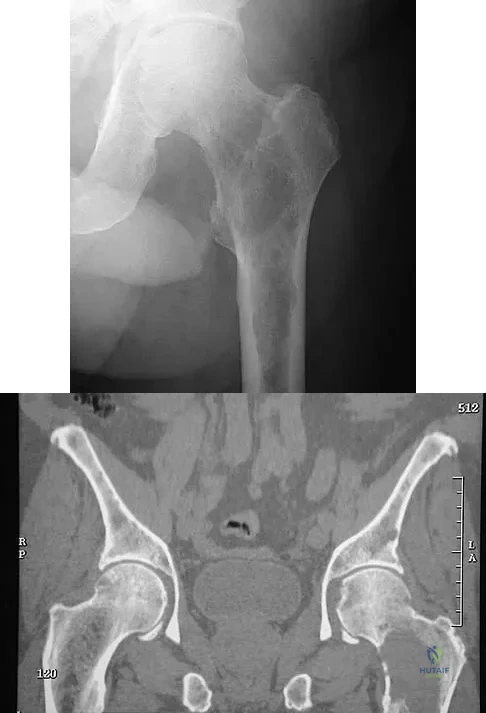

Question 62

A 46-year-old woman has bilateral groin pain, with more severe pain on the left side than on the right side. Figures 44a and 44b show a radiograph and a T1-weighted MRI scan. What is the most likely diagnosis?

Explanation

Question 63

Figures 29a and 29b show the AP radiograph and CT scan of a 70-year-old man who has left thigh pain. Serum protein electrophoresis shows a monoclonal gammopathy. Additional radiographs of the femur show other lesions. Management should consist of

Explanation